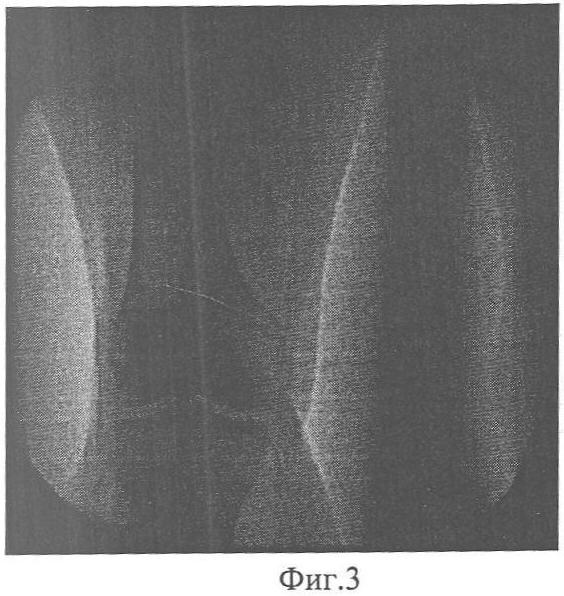

Фиг.1 – ангиограмма конечности больного П. до лечения;

Выполнена диагностическая артериография левой нижней конечности. На артериограмме определяется окклюзия левой подколенной артерии в средней порции. Дистальнее контрастируется подколенная артерия с начальными отделами берцовых артерий. Средняя треть голени и стопа аваскулярны (Фиг.1, 2).